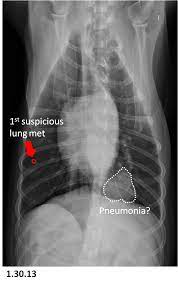

Harry proved that life could be great on 3, even with cancer. A dog's life expectancy at this point can be hours to days. The life expectancy of a dog diagnosed with lung cancer can be up to 22 months, depending on the type of tumor and on the treatment the dog undergoes. Dogs with metastatic lung cancers generally have several tumors in the lungs, not just a single growth. Prognosis of dog lung cancer depends on a number of actors, such as the dog's age, health condition, and whether the cancer has spread to other locations (e.g.

What Is Metastasis In Dogs from files.brief.vet If the lymph nodes are involved or multiple tumors are found at the time of diagnosis, survival time is shortened to only 2 months. Dogs with high grade (poorly differentiated) tumors with lymph node involvement have an average survival of three months, even with surgery. It's ok to cry and feel sad about the situation, but this is the time to stay strong. The life expectancy of a dog diagnosed with lung cancer can be up to 22 months, depending on the type of tumor and on the treatment the dog undergoes. For dogs with small, low grade (well differentiated) tumors without lymph node involvement, the average survival time is 16 months or longer with surgery alone. If your dog already has evidence of cancer in other abdominal organs or in the lungs, the prognosis is grave and your dog may only have a few weeks left. Gatsby, her smallest dog, wasn't the brightest, but he was always happy.. The best prognosis is seen in dogs with solitary lesions that are less than 2 inches in diameter.

Lung Cancer In Dogs Causes Signs Treatment Canna Pet from g77v3827gg2notadhhw9pew7-wpengine.netdna-ssl.com Our dog has cancer and we're not treating it. By definition, the final stage of lung cancer implies that treatment options have been exhausted; With treatment, survival time is about 12 months. If the lymph nodes are involved or multiple tumors are found at the time of diagnosis, survival time is shortened to only 2 months. Dogs with metastatic lung cancers generally have several tumors in the lungs, not just a single growth. Harry proved that life could be great on 3, even with cancer. It's ok to cry and feel sad about the situation, but this is the time to stay strong. Another interesting thing to note is that dogs with short or medium snouts seem to be more prone to developing lung cancers.

If your dog is 8, and the average lifespan for his weight and breed is 10 years, and your veterinarian tells you that his survival time for his cancer is about 18 months to two years, and calls that a long time, he's right from a medical perspective. Joanna my dog was diagnosed with lung cancer last week. A cure is not possible. Harry proved that life could be great on 3, even with cancer. The best way to increase a dog's prognosis against metastatic cancer is to be aware of the signs and to detect it early enough that treatment can be successful. With treatment, survival time is about 12 months. The best prognosis is seen in dogs with solitary lesions that are less than 2 inches in diameter. If the lymph nodes are involved or multiple tumors are found at the time of diagnosis, survival time is shortened to only 2 months. How long can dogs live with metastatic cancer and metronomic chemotherapy?one of the most devastating things is finding out your dog or cat's cancer has meta. Your dog's tumor probably originated in his bones as osteosarcoma, in his mouth as oral melanoma, or in the blood vessels as hemangiosarcoma. A dog with a single primary lung tumor that has not spread to the lymph nodes has the longest average survival time (an average of 12 months); When tumors are in the early stage, can undergo surgical removal, and have not even come close to spreading to other parts of the body, dogs are expected to live for roughly twenty months. The prognosis for primary lung cancer varies, and can be very difficult to predict for an individual dog.